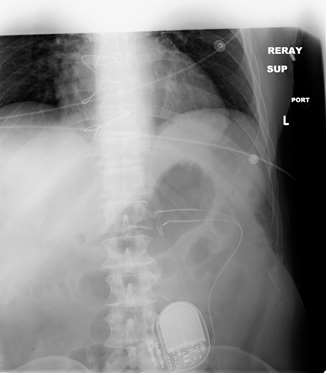

x-ray view of implanted gastric pacemaker

Figure 1: X-ray view of implanted system